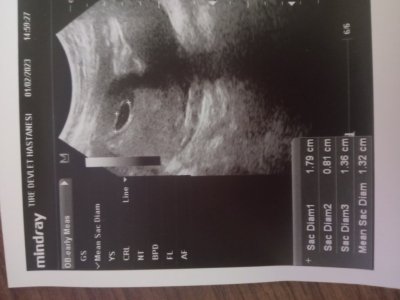

Geçen hafta hamile kaldığımı öğrendim ama bundan önce kimyasal bir gebelik geçirdiğim için hastaneye koşturmak istemedim. Reglimin üstünden tam 8 gün geçti yani adetimin ilk gününe göre 5 hafta 1 günlük hamile olduğumu hesapladım. Bugün beta hcg testi yaptırdım sonucum 11.381 çıktı. Bu haftaya göre biraz fazla değilmi sizce ? Hala doktora gitmedim eşimle konuştuk haftaya gidersek kalp atışlarını da duyarız diye planladık. Sizin değerleriniz neydi benimle aynı durumu yaşayan varmı acaba ? İlgilenirseniz çok sevinirim

Geçen hafta hamile kaldığımı öğrendim ama bundan önce kimyasal bir gebelik geçirdiğim için hastaneye koşturmak istemedim. Reglimin üstünden tam 8 gün geçti yani adetimin ilk gününe göre 5 hafta 1 günlük hamile olduğumu hesapladım. Bugün beta hcg testi yaptırdım sonucum 11.381 çıktı. Bu haftaya göre biraz fazla değilmi sizce ? Hala doktora gitmedim eşimle konuştuk haftaya gidersek kalp atışlarını da duyarız diye planladık. Sizin değerleriniz neydi benimle aynı durumu yaşayan varmı acaba ? İlgilenirseniz çok sevinirim